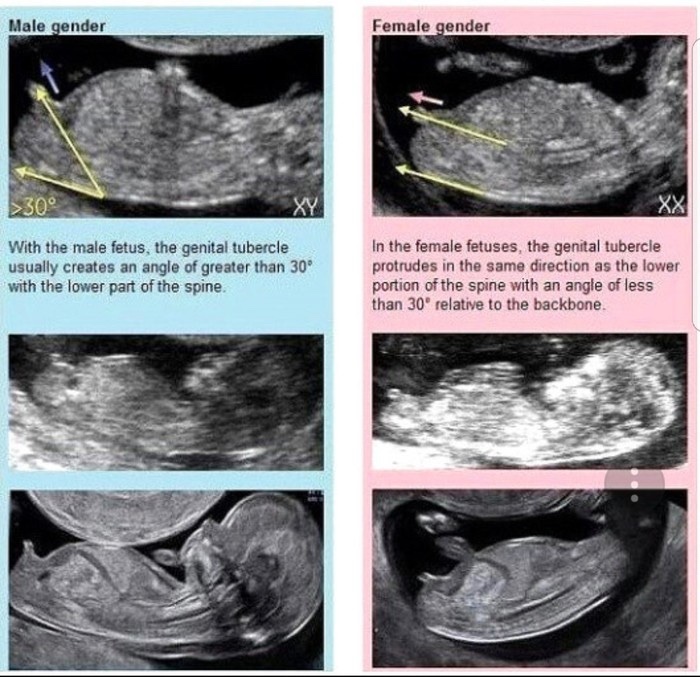

초음파 각도법이란?

초음파 생식기를 초반에 각도로 판단하여! 딸/아들을 구분 짓는 것. 실제로 얼마나 확률이 되는지 모르겠으나 나의 첫째는 이 각도법이 맞았음.

12주~14주 정도에는 남/녀 모두가 성기가 튀어나와 있어서 튀어나온 것으로는 보통 판별하지 않음

위 사진처럼

각도가 위로 치솟아 있으면 아들! 척추와 평평하면 딸!